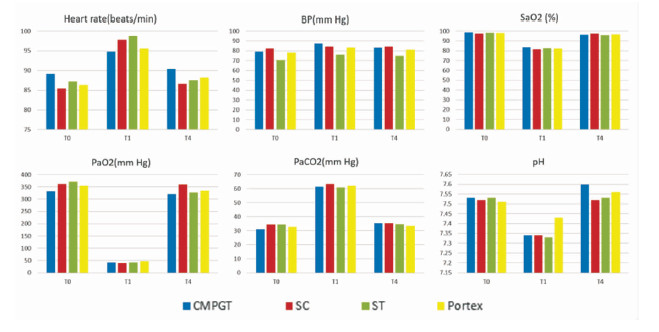

2 结果 2.1 时效性所有小型猪(20/20)均成功建立气道并通气。四组小型猪术后的心电监控和动脉血气指标并没有显著的组间差异,但是每组可见显著的术前和术后差异(P<0.05),表明四种方法均可以有效的恢复通气和供氧(图 1A)。ECG显示停止供氧后T波降低、QT间期缩短,可能与心率变化、交感神经过度活跃和心肌缺氧有关。SC、GWDF、CMPGT和ST的手术时间分别为(86±12)s,(165±63)s,(174±34)s和(519±128)s,但是CMPGT恢复通气的时间最短,为(23±4)s (P<0.01) (图 1)。这是因为一旦穿刺管通过环甲膜进入气管,既可以通过气囊打气供氧,而非像其他3种方法必须要插管后才能恢复通气。四组的SpO2从T2开始快速上升,并分别于(176±28)s(CMPGT),(189±17)s(SC),(240±43)s(GWDF)和(628±117)s(ST)时达到95%(图 1B)。CMPGT、SC、GWDF和ST组SpO2曲线的上升部分斜率分别为0.11、0.17、0.29和0.3,说明GWDF和ST组在建立气道插管后的通气能力要强于SC和CMPGT。但是需要注意的是CMPGT包括两个阶段的两种不同的通气方式,第一阶段通过穿刺管上的气孔通气(T2至T3),此时SpO2曲线的斜率为0.07;第二阶段通过气管造口处插管(T3至T4),SpO2曲线的斜率为2.75。由于穿刺管的直径较细(内径4 mm),通过穿刺管上气孔的通气能力不如气管造口后插管,但仍可以提供足够的通气,以便尽快的解除缺氧。CMPGT组的SpO2曲线和95% SpO2线间的面积最小(与GWDF和ST组相比P<0.01;与SC组相比P<0.05),说明CMPGT是四种方法里最具有时效性的手段(图 2)。小型猪的皮肤至气管的距离约为3~4 cm,人类一般为2 cm左右,同时小型猪皮肤质地更为坚韧,因此可以合理的推测将CMPGT用于患者时可能操作时间更短。

| 图 1 四组小型猪在同一时刻的心电监控和动脉血气指标 Fig 1 Ecg monitoring and arterial blood gas index at the same time |